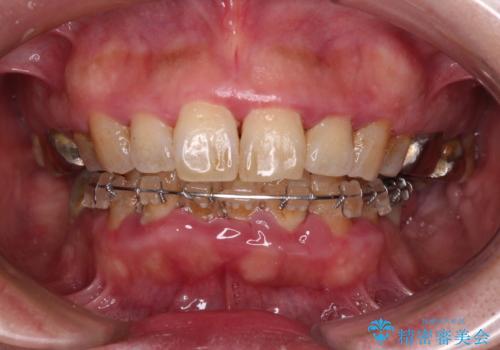

- インプラント治療を前提に下顎の部分矯正を始めたものの、そのまま長い間放置しているとのことで来院された患者様です。

全体的に歯肉が腫れており、歯周病により抜歯をしなければならない歯がある状態でした。

治療前は磨き残しが多く見られ、全体的に歯肉が腫れている状態でしたが、抜歯の必要な歯を抜いたことで口腔内の環境が改善され、磨き残しも少なくなってきました。